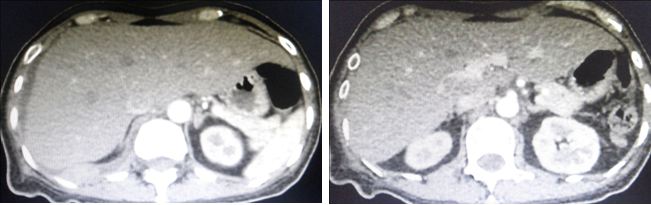

Ria came back to the same private hospital in Penang where she had her surgery. She was referred to the lung specialist. A CT was done and showed the following:

- There is a 5.5 x 5.1 x 3.5 cm mass in the manubrium sterni with an extension of the mass into the prevascular space of the mediastinum.

- There is moderate to large right pleural effusion (fluid in the lung).

- Collapse-consolidation of right lower lobe.

- Right and left main pulmonary arteries and their lobar branches are consistent with pulmonary embolism (PE).

From the pictures above, her breast cancer must have spread to her lungs, bone and liver. In addition she suffered DVT of the right leg. The doctor wanted Ria to be admitted into the hospital right away, to treat her DVT. She also refused.